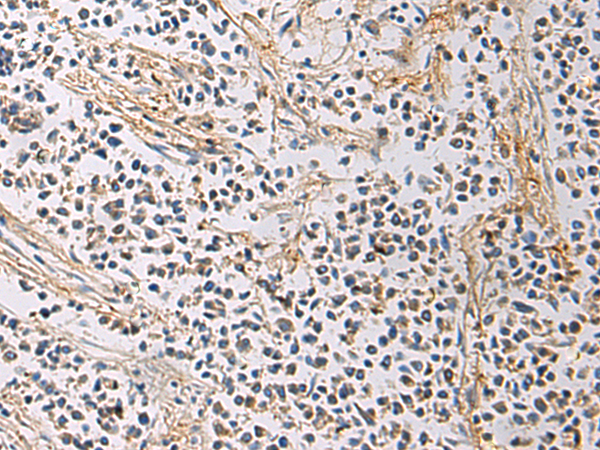

分类: 科研抗体货号: P10391别名: GMPR1; GMPR 1应用: IHC反应种属: Human, Mouse, Rat